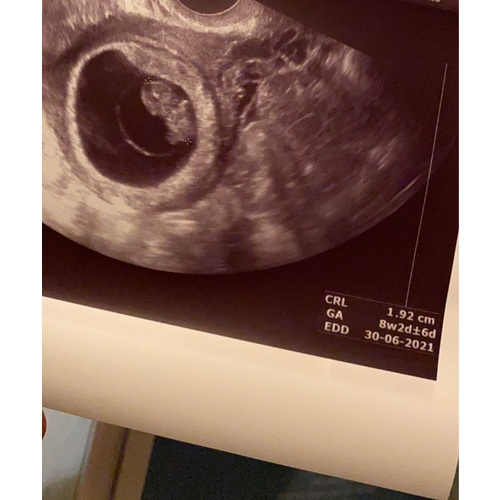

Ik dacht 7+3 te zijn gisteren. Kindje was op de echo 1,5cm groot. Op basis daarvan werd ik een beetje vooruit gezet en 7+6 geschat

Ik was gemeten op precies 8 weken. En mijn vruchtje was 1.67 cm

Hei daar heb ik nog nooit van gehoord had de echo van me schoonzus ook gezien op zelfde weken die had een hele andere maat. Ik zit op 8+3 op de echo. Ik ga het eens mijn verloskundige vragen want zie ook hier op topics andere mm ben wel benieuwd

Ze kunnen het precies zeggen rond de 11 weken. Elke mm kan zo maar 茅茅n dag langer of korter zijn.